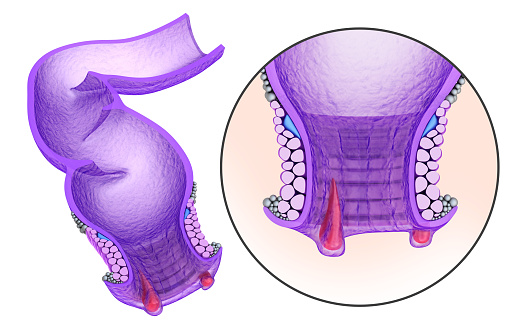

Having a twisted bowel is like having a twist or loop that results in the obstruction of fecal matter moving through the intestines. The medical term for the condition is volvulus, which can occur in the small or large intestine. It may be referred to as small bowel volvulus or colonic volvulus, respectively. Where the ...click here to read more